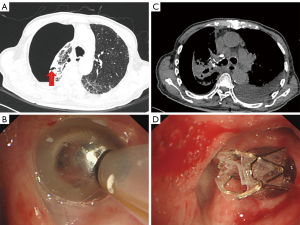

After antibiotic treatment, his chest CT showed a new pulmonary mass (3.1 cm × 1.8 cm) in the right upper hilum, which was considered a new metastatic lesion of lung cancer. Smear samples obtained by endobronchial ultrasound-guided transbronchial fine-needle aspiration (EBUS-TBNA) confirmed the presence of cancer cells. His doctor advised him to undergo a pneumonectomy, and tissue histopathology revealed inflammatory granulomas in the mediastinal pleural membrane and an aggressive adenocarcinoma in the RUL of the lung (rT2aN1M0, IIA). M. chelonae was confirmed in his lung lesion tissue by 16sRNA analysis. He was originally treated with amikacin and linezolid. Three months later, the chest CT showed an additional right hydro-pneumothorax (Figure 3A), and a chest tube was placed into the pleural cavity. However, a persistent air leak indicated a suspicious BPF. A multidisciplinary team evaluation was conducted involving a radiologist, physician, thoracic surgeon, and interventional pulmonologist. Finally, bronchoscopic interventional therapy was chosen as the patient was deemed inoperable. The suspected culprit bronchus was identified by instillation of methylene blue through a chest tube, and the Chartis monitoring system confirmed another fistulous tract located in the right B4a and B6a+c, with no bypass ventilation between them. The Amplatzer PDA device was used to manage the stump fistula. Using the 6F and 8F delivery systems, two PDA occluders (Heart RTM, Xianjian Technology (Shenzhen) Co., Ltd., China) were precisely released at the opening of the right B4a (XJFD0406) and B6a+c (XJFD0810) (Figure 3B-3D). No adverse event happened during the procedure.